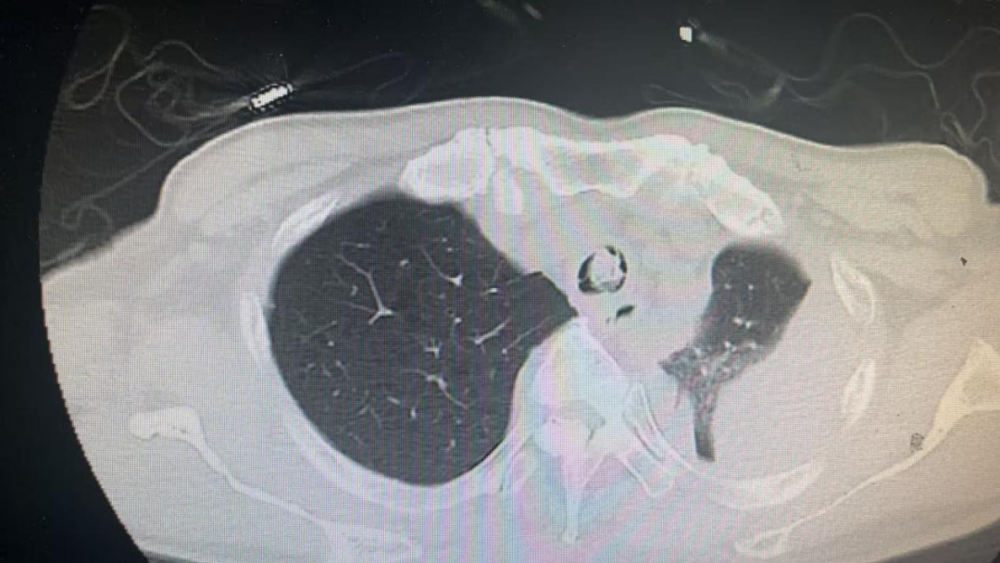

唐先生多年前因声带恶性肿瘤接受手术治疗并实施气管切开术。近日,突发严重憋气、喘息症状,在家尝试咳嗽及雾化治疗无效后,紧急转送至人民医院院区肿瘤消化科住院治疗。入院后,高流量吸氧下血氧饱和度仅80%左右,生命体征极不稳定。医院迅速组织呼吸老年科、内镜中心、ICU等多学科会诊,呼吸老年科曹辛瑜副主任评估发现患者主气道被巨大痰痂堵塞,随时可能导致窒息,立即决定实施急诊气管镜介入治疗。呼吸老年科团队成功取出长约4厘米、最宽处达2.5厘米的巨型痰栓。术后,唐先生憋气症状迅速缓解,血氧饱和度回升并稳定在99%,生命体征平稳。